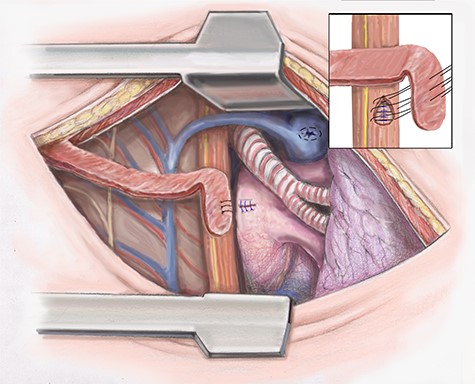

Attention is then turned to the esophageal repair. The necrotic tissue is further debrided. The esophagus is closed in two layers. The inner serosal layer is repaired using a running 4–0 PDS suture. The outer muscular layer is repaired with interrupted 3–0 silk (Fig. 3).

Artist illustration shows closure of esophageal portion of fistula and intercostal muscle flap placement.

To separate the repairs the intercostal muscle flap previously harvested is positioned. If the blood supply of the intercostal muscle is damaged, we then use the latissimus muscle, which was spared in the thoracotomy. The muscle flap is sutured in place (Fig. 3). The chest is drained widely using chest tubes and closed in a standard fashion.